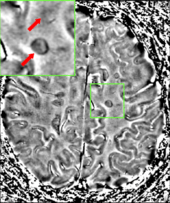

The name multiple sclerosis refers to the scars (sclerae – better known as plaques or lesions) that form in the nervous system. These lesions most commonly affect the white matter in the optic nerve, brain stem, basal ganglia, and spinal cord, or white matter tracts close to the lateral ventricles.[2] The function of white matter cells is to carry signals between grey matter areas, where the processing is done, and the rest of the body. The peripheral nervous system is rarely involved.[3]

To be specific, MS involves the loss of oligodendrocytes, the cells responsible for creating and maintaining a fatty layer—known as the myelin sheath—which helps the neurons carry electrical signals (action potentials).[2] This results in a thinning or complete loss of myelin and, as the disease advances, the breakdown of the axons of neurons. When the myelin is lost, a neuron can no longer effectively conduct electrical signals.[3] A repair process, called remyelination, takes place in early phases of the disease, but the oligodendrocytes are unable to completely rebuild the cell's myelin sheath.[41] Repeated attacks lead to successively less effective remyelinations, until a scar-like plaque is built up around the damaged axons.[41] These scars are the origin of the symptoms and during an attack magnetic resonance imaging (MRI) often shows more than ten new plaques.[2] This could indicate that there are a number of lesions below which the brain is capable of repairing itself without producing noticeable consequences.[2] Another process involved in the creation of lesions is an abnormal increase in the number of astrocytes due to the destruction of nearby neurons.[2] A number of lesion patterns have been described.[42]

Clinical data alone may be sufficient for a diagnosis of MS if an individual has had separate episodes of neurological symptoms characteristic of the disease.[46] In those who seek medical attention after only one attack, other testing is needed for the diagnosis. The most commonly used diagnostic tools are neuroimaging, analysis of cerebrospinal fluid and evoked potentials. Magnetic resonance imaging of the brain and spine may show areas of demyelination (lesions or plaques). Gadolinium can be administered intravenously as a contrast agent to highlight active plaques and, by elimination, demonstrate the existence of historical lesions not associated with symptoms at the moment of the evaluation.[46][48] Testing of cerebrospinal fluid obtained from a lumbar puncture can provide evidence of chronic inflammation in the central nervous system. The cerebrospinal fluid is tested for oligoclonal bands of IgG on electrophoresis, which are inflammation markers found in 75–85% of people with MS.[46][49] The nervous system in MS may respond less actively to stimulation of the optic nerve and sensory nerves due to demyelination of such pathways. These brain responses can be examined using visual- and sensory-evoked potentials.[50]